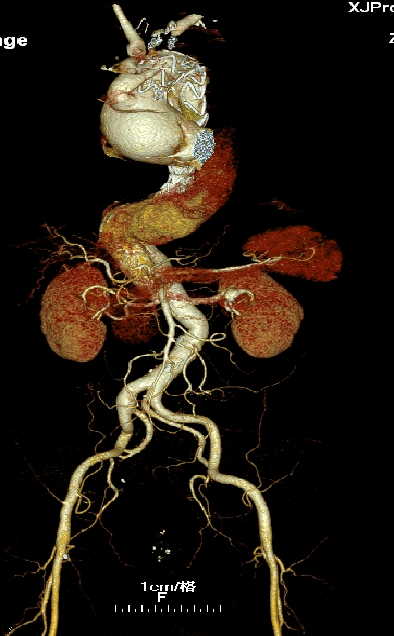

男, 49岁,急性夹层 。2018年11月TEVAR。一月后复查:RTAD 。 2019年1月双开窗。2019年4月2日 复查,结果良好。